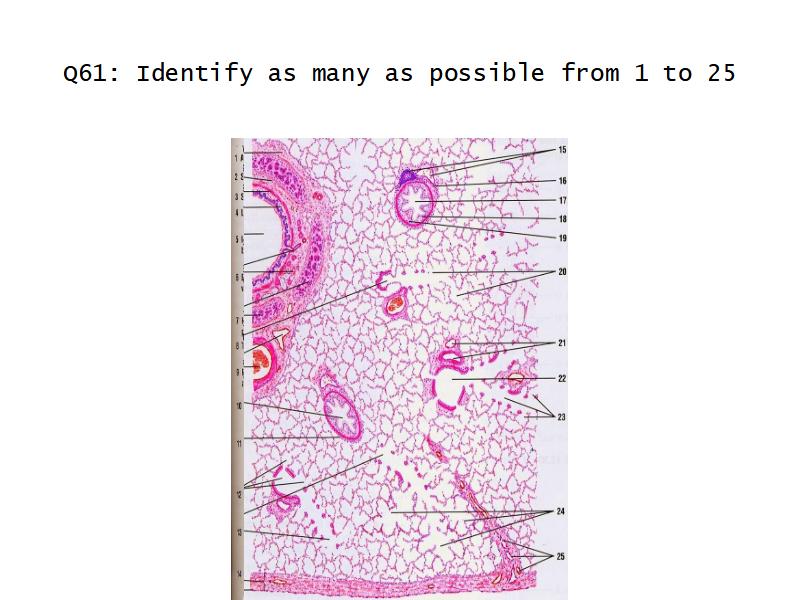

Slides: Respiratory System

- Slide 71: Nostril

- Slide 72 & 74: Lung

- Slide 73: Trachea

- Slide 108: Olfactory epithelium

- Slide 111: Epiglottis

Lungs